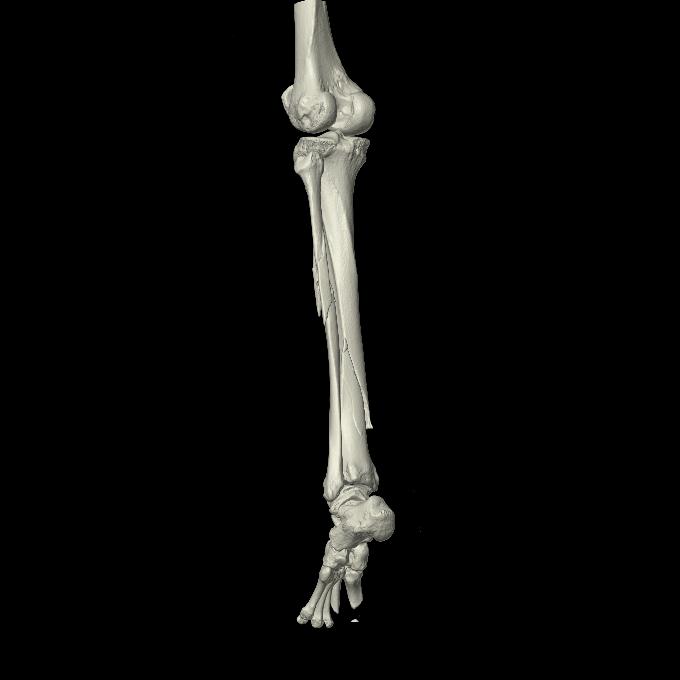

102803 1/12(キウスなし) 1/27 左下腿 4R 30歳女性 左脛骨軸内釘